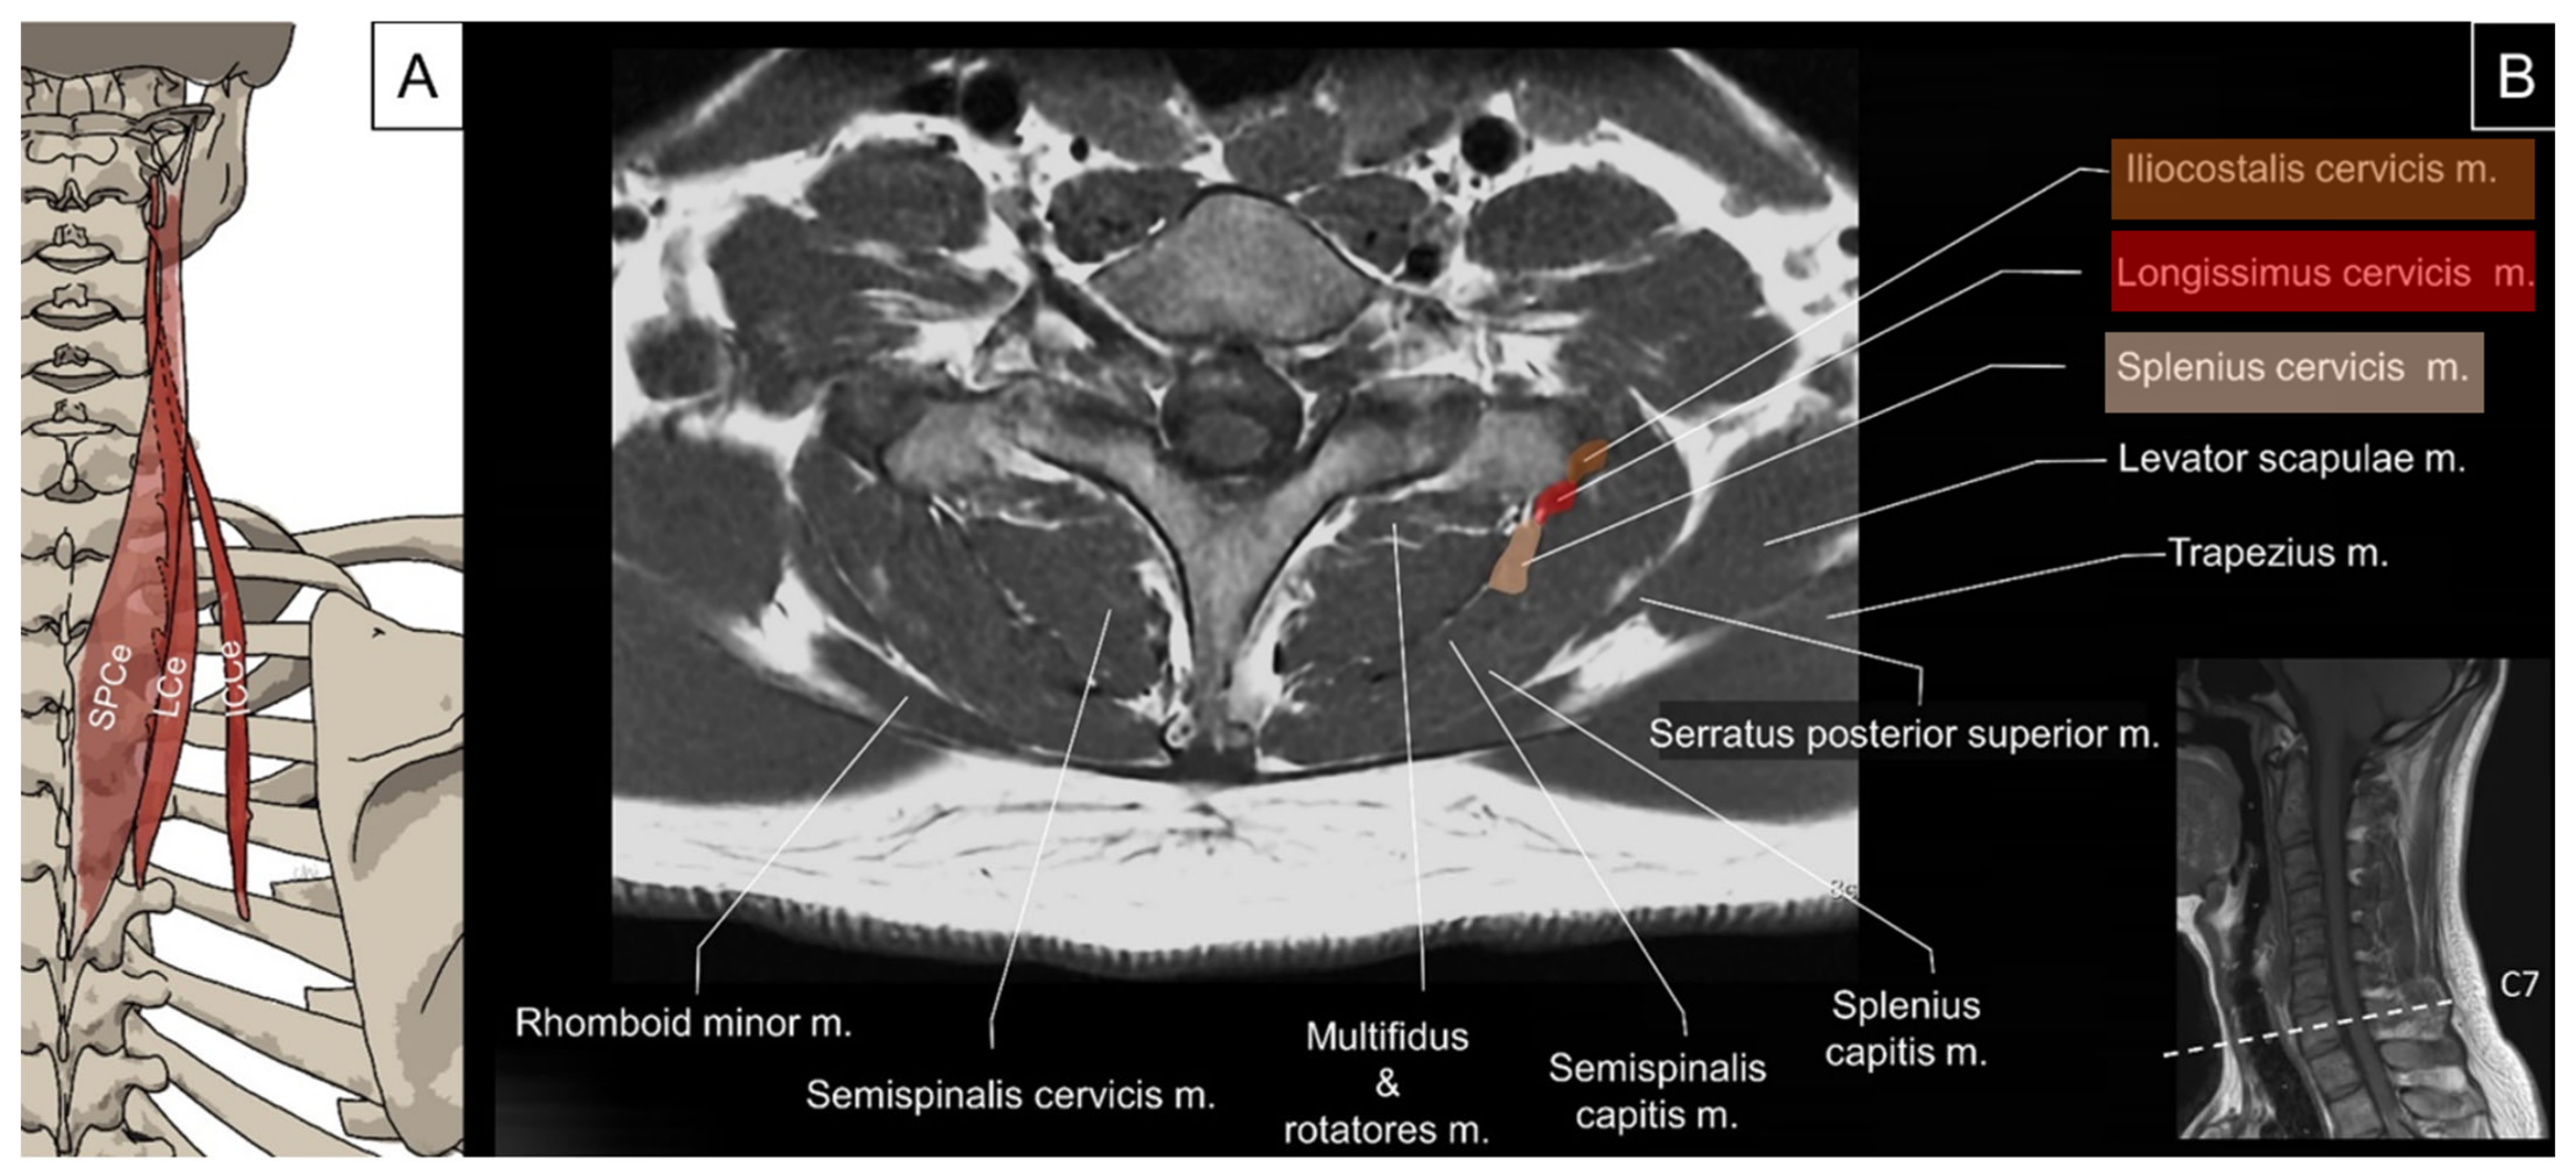

4.2. Iliocostalis/Longissimus/Splenius Cervicis

4.2.1. Anatomy

4.2.2. Sonographic Scanning

4.2.3. Clinical Relevance